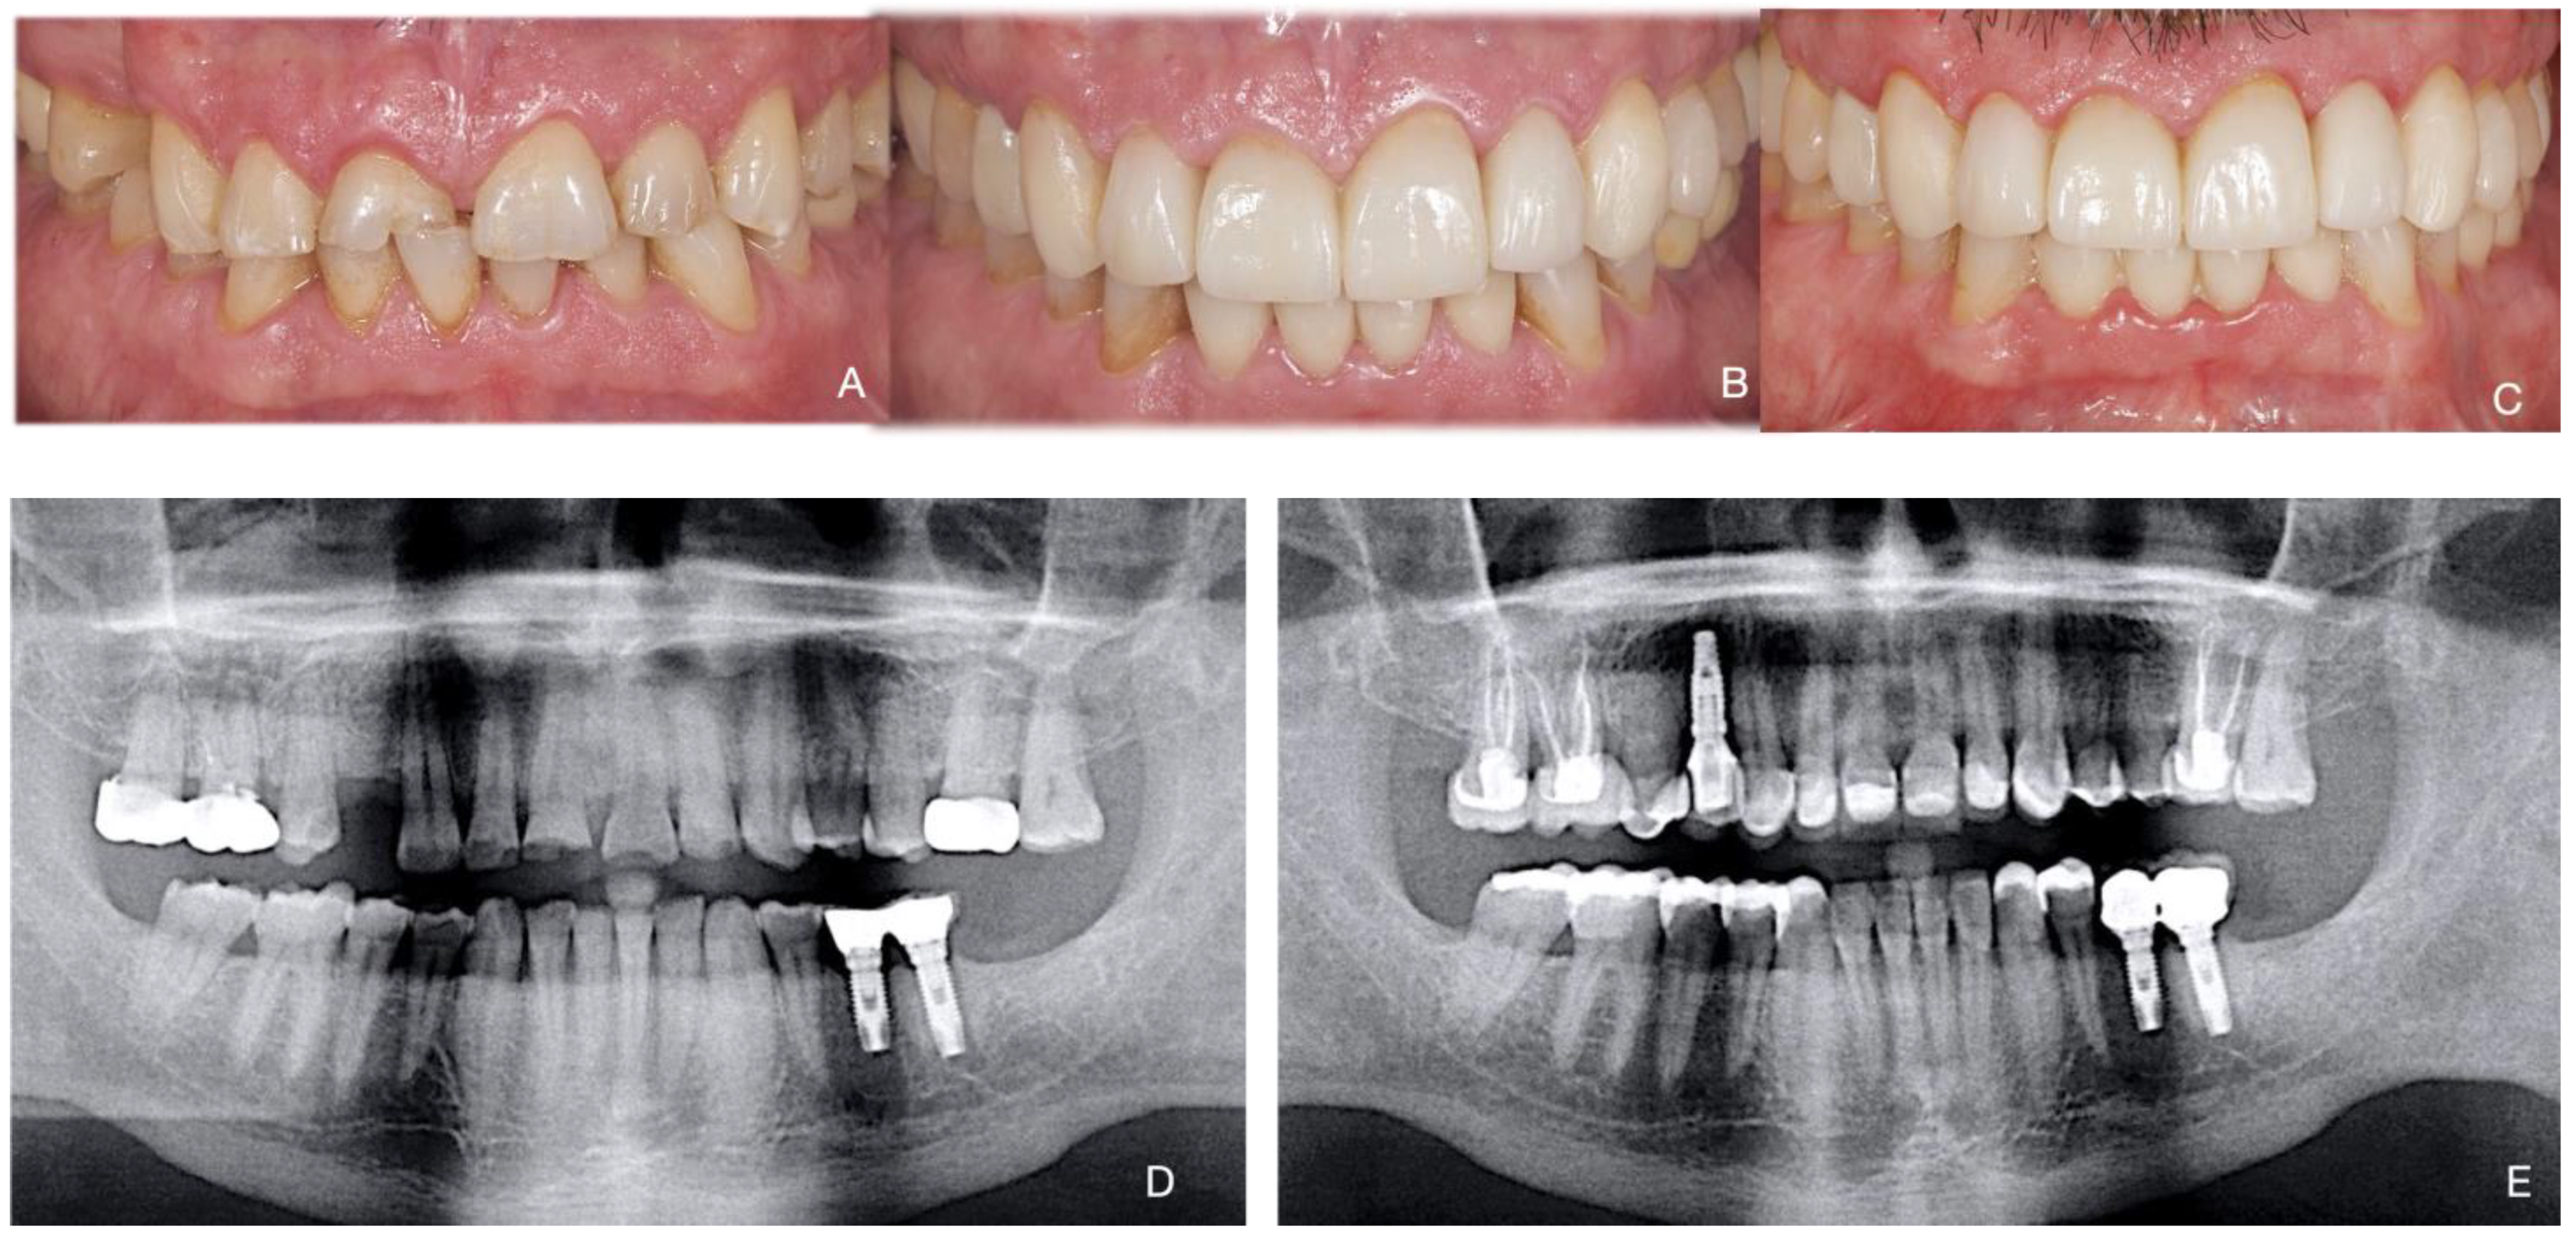

Total Rehabilitation Using Adhesive Dental Restorations in Patients with Severe Tooth Wear: A 5-Year Retrospective Case Series Study

3. Results